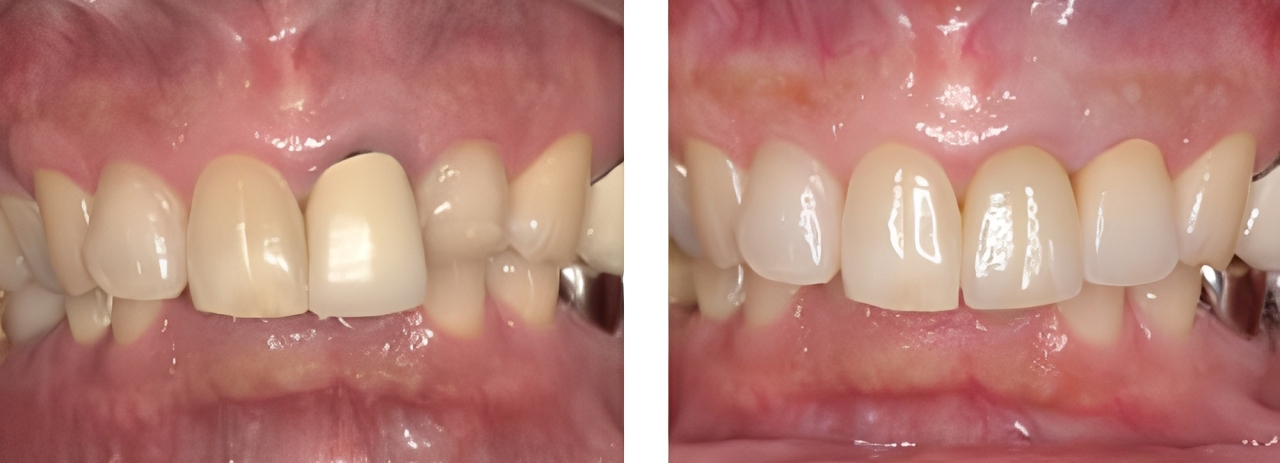

審美歯科

術前

術後

| 治療内容 | ウォーキングブリーチ後ジルコニアセラミックにて治療を行った |

|---|---|

| 治療期間・回数 | 4カ月・10回 |

| 費用 ※自由診療となります |

ウォーキングブリーチ:11,000円 プロビジョナルレストレーション:2,200円 ファイバーコア:16,500円 ジルコニアセラミック:132,000円 |

| リスク・副作用 |

|